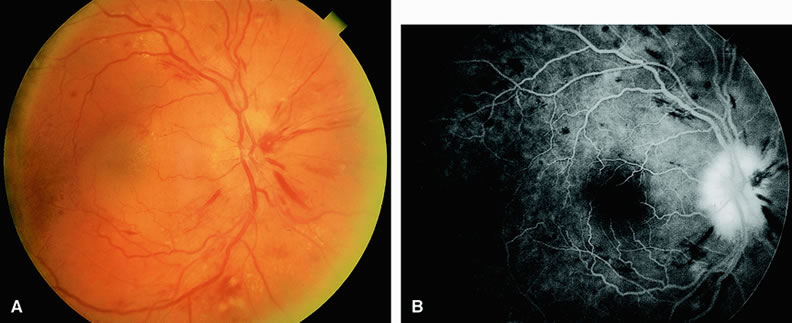

PERIPHERAL PROLIFERATIVE RETINOPATHIES The most common cause of peripheral proliferative retinopathy is sickling hemoglobinopathies. They account for approximately one half of cases.17 Among patients with sickling hemoglobinopathy and peripheral proliferative retinopathy, hemoglobin SC is the most common variant. Other causes of peripheral proliferative retinopathy include retinal vein branch obstruction, diabetes mellitus, sarcoidosis, intravenous drug abuse, and Eales' disease.17 On fluorescein angiography, the posterior pole and the optic nerve often appear normal. Peripheral retinal capillary nonperfusion is seen in most eyes with peripheral extraretinal neovascularization.17,18 Shutdown of the larger peripheral retinal vessels is also often observed. Peripheral retinal neovascularization can assume several configurations, although the most common variant is that of the “sea fan” characteristic of sickle-cell retinopathy18 (Fig. 14). The angiogram demonstrates leakage of dye into the vitreous from these sites of neovascularization. In eyes in which scatter panretinal photocoagulation is being considered to control peripheral neovascularization, fluorescein angiography helps identify the regions of retinal capillary nonperfusion that require treatment. COATS' DISEASE Coats' disease19 is a retinal vascular abnormality of unknown etiology characterized by retinal telangiectatic formations in association with intraretinal and subretinal hard exudates (Fig. 15). Focal areas of dilation and narrowing of the larger retinal vessels are often seen. Fluorescein angiography20 demonstrates hyperfluorescence of the telangiectatic vessels early in the study along with hypofluorescence of proteinaceous exudates and mild hyperfluorescence of subretinal fluid. Enlargement of the retinal capillary bed and widened spaces between these small vessels is characteristic of Coats' disease. Retinal capillary nonperfusion is often seen, but associated retinal neovascularization is rare. Leakage of dye can occur from both the larger and smaller vessel abnormalities. RETINAL ARTERIAL MACROANEURYSM A retinal arterial macroaneurysm is an area of focal dilation, and often outpouching, along the course of an artery. First described by Robertson2 in 1973, the abnormality is often associated with systemic arterial hypertension and is found in older people, more commonly in women. More than one retinal arterial macroaneurysm may be present. Macroaneurysms most often occur in the superotemporal or the inferotemporal retinal arterial arcades, often after the second or third arteriolar branching. Local ocular complications include bleeding and the extravasation of serum and lipid into the surrounding retina.22 Blood from leaking macroaneurysms can extend into the vitreous cavity, retina, and/or subretinal space (Fig. 16). Fluorescein angiography in eyes with an acquired retinal arterial macroaneurysm generally reveals relatively early and late hyperfluorescence of the abnormality. The hyperfluorescence usually increases as the study progresses. There is often narrowing of the vessels proximal and distal to the macroaneurysm. The retinal capillary bed surrounding the macroaneurysm is often dilated, and leakage from local telangiectatic and microaneurysmal abnormalities is often present. Identification of coexistent leaking vessels is important if laser therapy is being considered. The macroaneurysm is often obscured by an overlying hemorrhage. Occasionally, the macroaneurysm can thrombose and lead to obstruction of the retinal artery distal to it. SYSTEMIC ARTERIAL HYPERTENSION Chronic systemic arterial hypertension manifests in the fundus with focal and diffuse retinal arterial narrowing; retinal hemorrhages; cotton-wool spots; and in more severe or acute cases, lipid exudate23 (Fig. 17). The lipid exudates may be deposited in a radial pattern surrounding the macula, forming the so-called macular star. In extreme cases (malignant hypertension), optic disc swelling is also present. Small yellow spots at the level of the retinal pigment epithelium resulting from underlying damage of the choriocapillaris can also be seen. Fluorescein angiography of eyes with acute hypertensive changes shows irregular-appearing constricted arterioles and focal areas of hypofluorescence resulting from retinal capillary nonperfusion in areas corresponding to cotton-wool spots. Telangiectatic retinal vascular abnormalities and microaneurysms often surround the cotton-wool spots and leak dye into the retina as the study progresses. In some instances, large areas of retinal capillary nonperfusion are present. The optic disc is usually hyperfluorescent in eyes with nerve-head swelling and malignant hypertension (see Fig. 17). Focal areas of hyperfluorescence resulting from leakage at the level of the choriocapillaris can also be seen. These areas eventually resolve, leaving pigmented and depigmented foci (Elschnig spots) at the retinal pigment epithelial level.24 Despite findings on fluorescein angiography, ophthalmoscopic evaluation is more important in making the diagnosis. Fluorescein angiography is also not needed for treatment (that is, controlling blood pressure). RADIATION RETINOPATHY The ophthalmic community has long appreciated that radiation is an effective therapeutic option for many intraorbital, periorbital, and intracranial neoplasms. In 1933 in the first reported case of radiation retinopathy, Stallard25 described the potentially harmful effects of radiation on the retina. At that time, clinicians used large doses of radiation, and little effort was made to limit radiation exposure of nonpathologic tissue. In recent years, technologic advances have enabled clinicians to administer radiation in lower doses by using delivery systems that limit exposure of radiation to normal tissue. Although these new approaches have helped reduce the incidence of radiation retinopathy, cases of radiation retinopathy continue to be reported. Radiation retinopathy slowly progresses and usually develops over months after exposure to ionizing radiation. External beam irradiation, 60Co plaque irradiation, and brachytherapy can all cause radiation retinopathy.26 The minimum amount of radiation capable of inducing retinopathy is controversial. Investigators have reported that as little as 1100 cGy can result in retinal damage.27 Amoaku and Archer28 recommend regularly screening all patients who have received at least 3000 cGy of radiation to the eye and closely observing all patients who have been exposed to 5000 cGy or more of radiation to the eye. Brown and colleagues26 reviewed 32 cases of radiation-induced retinopathy. In this group, 20 eyes had been exposed to 60Co plaque irradiation and 16 eyes had been exposed to external beam radiation. As shown in Table 3, hard exudates, microaneurysms, and intraretinal hemorrhages are the most common ophthalmoscopic manifestations of radiation-induced retinopathy. Brown and associates observed a discrepancy in the percentages of eyes developing hard exudates between the two modalities of radiation exposure.